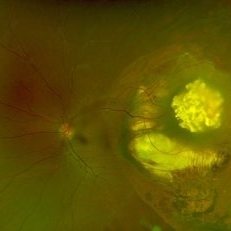

Optos widefield image of left eye of a 31 year old male c/o defective vision in left eye since 6 years with esotropia of 30 degree. Fundus shows translucent greyish mass temporal to macula surrounded by zone of atrophy with pigmentation. Right eye fundus within normal limits.

Photographer: Mr. Vedavyasa N K

Imaging device: Optos

Condition/keywords: optos, Retinoma, spontaneously regressed retinoblastoma